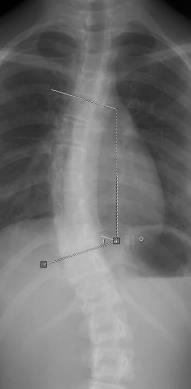

Use the Angle option to measure the angle between two intersecting lines on an image or the angle between two lines that do not intersect such as an angle of a spine deformity. Example A is Cobb Angle.

Example A

• Click the starting point of the second line and drag to the second end point. A dotted line connects the two line and calculates the angle (Cobb angle) between them.

For the 4 point angle, a dotted line automatically connects the two lines and calculates the angle in degrees between them.